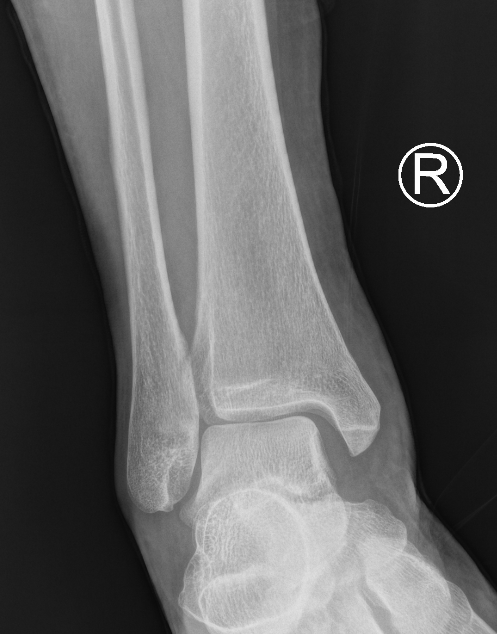

Weber B fibular fracture

Definition

Fracture at level of syndesmosis

Supination-external rotation Type IV

Syndesmosis stable - management depends on deltoid ligament

Deltoid ligament assessment

Mortise view

- symmetrical space around mortise

- AP with 15 degrees internal rotation

Increased medial clear space / lateral talar shift / deltoid ligament injury